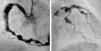

Right and left coronary angiography showing severe diffuse aneurysmal coronary artery disease. (A) Selective right coronary angiogram in left anterior oblique view showing a large aneurysm involving the proximal and mid segments of the right coronary artery (maximum diameter 12mm) as well as multiple smaller aneurysms in the distal segment of the vessel and in the posterolateral branch. (B) Selective left coronary angiogram in right anterior oblique view showing multiple aneurysms involving the distal portion of the left main coronary artery (LMCA), the proximal and mid segments of the left anterior descending (LAD) coronary artery and the proximal segment of the circumflex and the marginal branch.